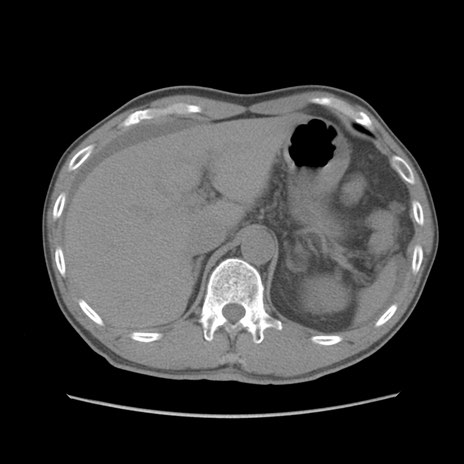

症例56 CT(横断像)

脂肪ウインドウ